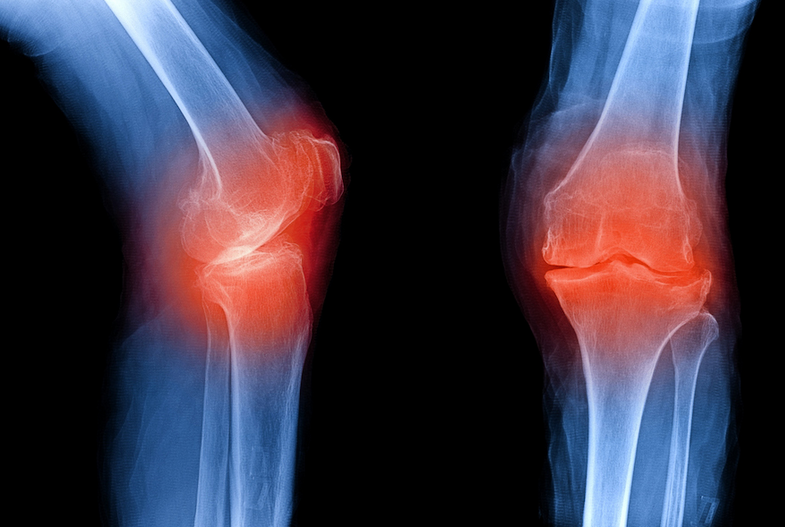

In a healthy joint, cartilage acts as a smooth cushion between bones. In osteoarthritis:

- cartilage becomes thinner and rougher

- bones may rub together

- joint shape can change

- movement becomes painful and stiff

Rheumatoid arthritis (RA) is a chronic autoimmune disease. Unlike osteoarthritis, it is not caused by joint wear and tear. Instead, the immune system mistakenly attacks the lining of the joints, causing inflammation.

Over time, this inflammation can:

- damage cartilage and bone

- deform joints